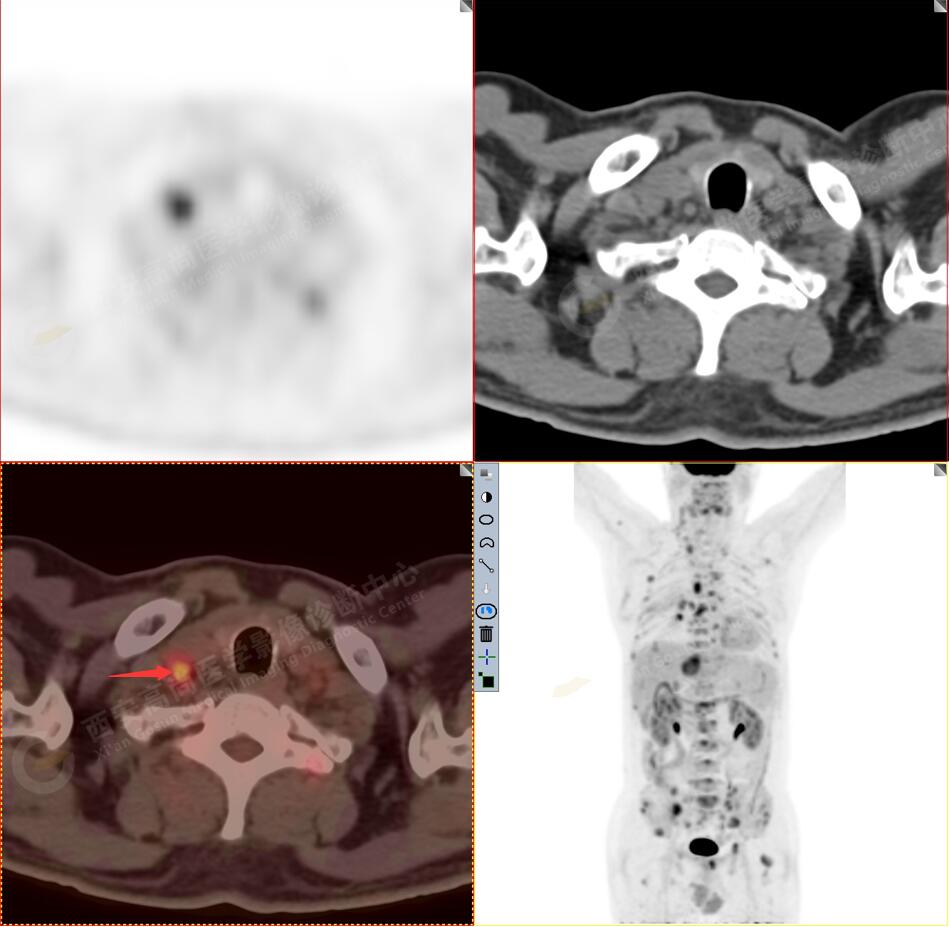

病史:男性,61歲,咳嗽1月余,CT發(fā)現(xiàn)肺結節(jié)。外院腋窩淋巴結穿刺活檢提示:轉移性腺癌。行PET/CT進行腫瘤分期。

1.右肺中葉內(nèi)側段軟組織結節(jié),呈淺分葉狀,邊緣可見毛刺及胸膜牽拉征,呈FDG代謝異常增高,考慮為周圍型肺癌。

3.右側頸部(Ⅱ-Ⅴ區(qū))、右側腋窩區(qū)、右側肺門及縱隔(1R、1L、2、4、6、7組)、肝門區(qū)多發(fā)腫大淋巴結,呈不同程度異常增高,均考慮為淋巴結轉移。